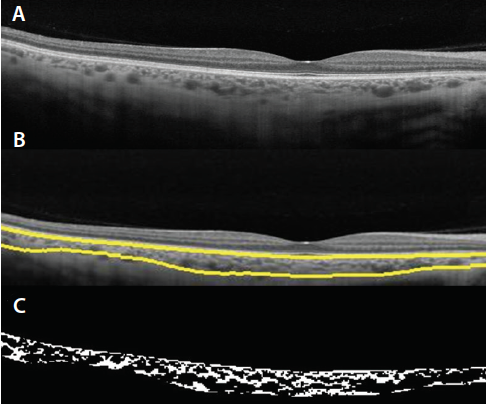

Figure 5. SS-OCT images of disease entities related to the pachychoroid spectrum: patient with PPE with disrupted ellipsoid zone and drusen-like deposit with no subretinal fluid (A); patient with CSCR, subretinal fluid, and elongated photoreceptors (B). SS-OCT scan of a patient with PNV with subretinal pigment epithelium neovascularization, subretinal fluid, and exudation (C).

Pachychoroid Spectrum

Disease entities with abnormally thickened choroid comprise the pachychoroid spectrum. These entities were described based on distinct clinical findings obtained through the use of EDI-OCT or SS-OCT imaging. They include pachychoroid pigment epitheliopathy (PPE), CSCR, pachychoroid neovasculopathy (PNV), and PCV (Figure 5).47 An interesting finding in these eyes is the presence of pachyvessels, which are characterized by a thickened Haller layer with compression of the Sattler layer and choriocapillaris.47